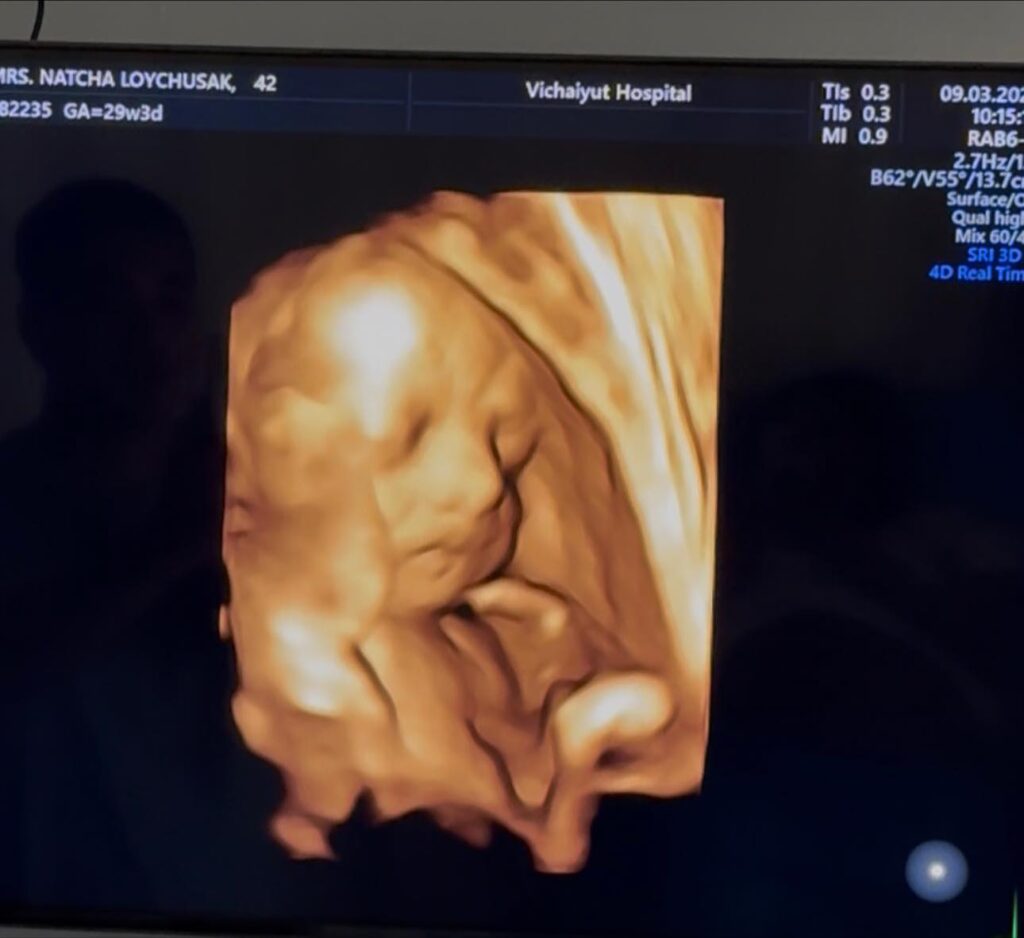

ล่าสุดครูก้อยได้ออกมาอัปเดตพัฒนาการของลูกน้อยในครรภ์ “น้องมีเมตตา” หลังเข้าพบแพทย์ตามนัด พร้อมอัลตราซาวด์ตรวจสุขภาพ โดยระบุว่าขณะนี้การตั้งครรภ์กำลังเข้าสู่ ช่วงไตรมาสสุดท้าย

โดยครูก้อยเผยว่า ขณะนี้อายุครรภ์อยู่ที่ 29 สัปดาห์ และข่าวดีคือ “น้องมีเมตตากลับหัวเรียบร้อยแล้ว” ซึ่งถือเป็นสัญญาณที่ดีของการเตรียมตัวเข้าสู่ช่วงโค้งสุดท้ายของการตั้งครรภ์

ผลตรวจจากแพทย์ระบุว่า น้ำหนักเบบี๋ 1,356 กรัม อยู่ในเกณฑ์มาตรฐาน ปริมาณน้ำคร่ำดี รกเกาะตำแหน่งปกติ และการไหลเวียนเลือดไปเลี้ยงสายสะดือดี โดยภาพรวมแพทย์ประเมินว่า สุขภาพของทารกในครรภ์แข็งแรงสมบูรณ์ดี

ขณะที่คุณพ่ออย่าง เจมส์ เรืองศักดิ์ ก็ได้โพสต์ผ่านเฟซบุ๊ก Raungsak James Loychusak อัปเดตภาพอัลตราซาวด์ของลูกสาวคนที่สอง “น้องมีเมตตา” ที่กำลังเติบโตแข็งแรงในครรภ์ พร้อมข้อความที่ทำเอาแฟน ๆ ยิ้มตาม

“น้องมีเมตตา ในวัย 29 สัปดาห์ 4 วัน พัฒนาการดีตามเกณฑ์ น้องกลับหัวแล้ว ดูทรงท่าจะขี้อ้อนปะป๊าเหมือนพี่สาวเธอแน่ ๆ ปะป๊าเตรียมใจละลายอีกคูณสอง”